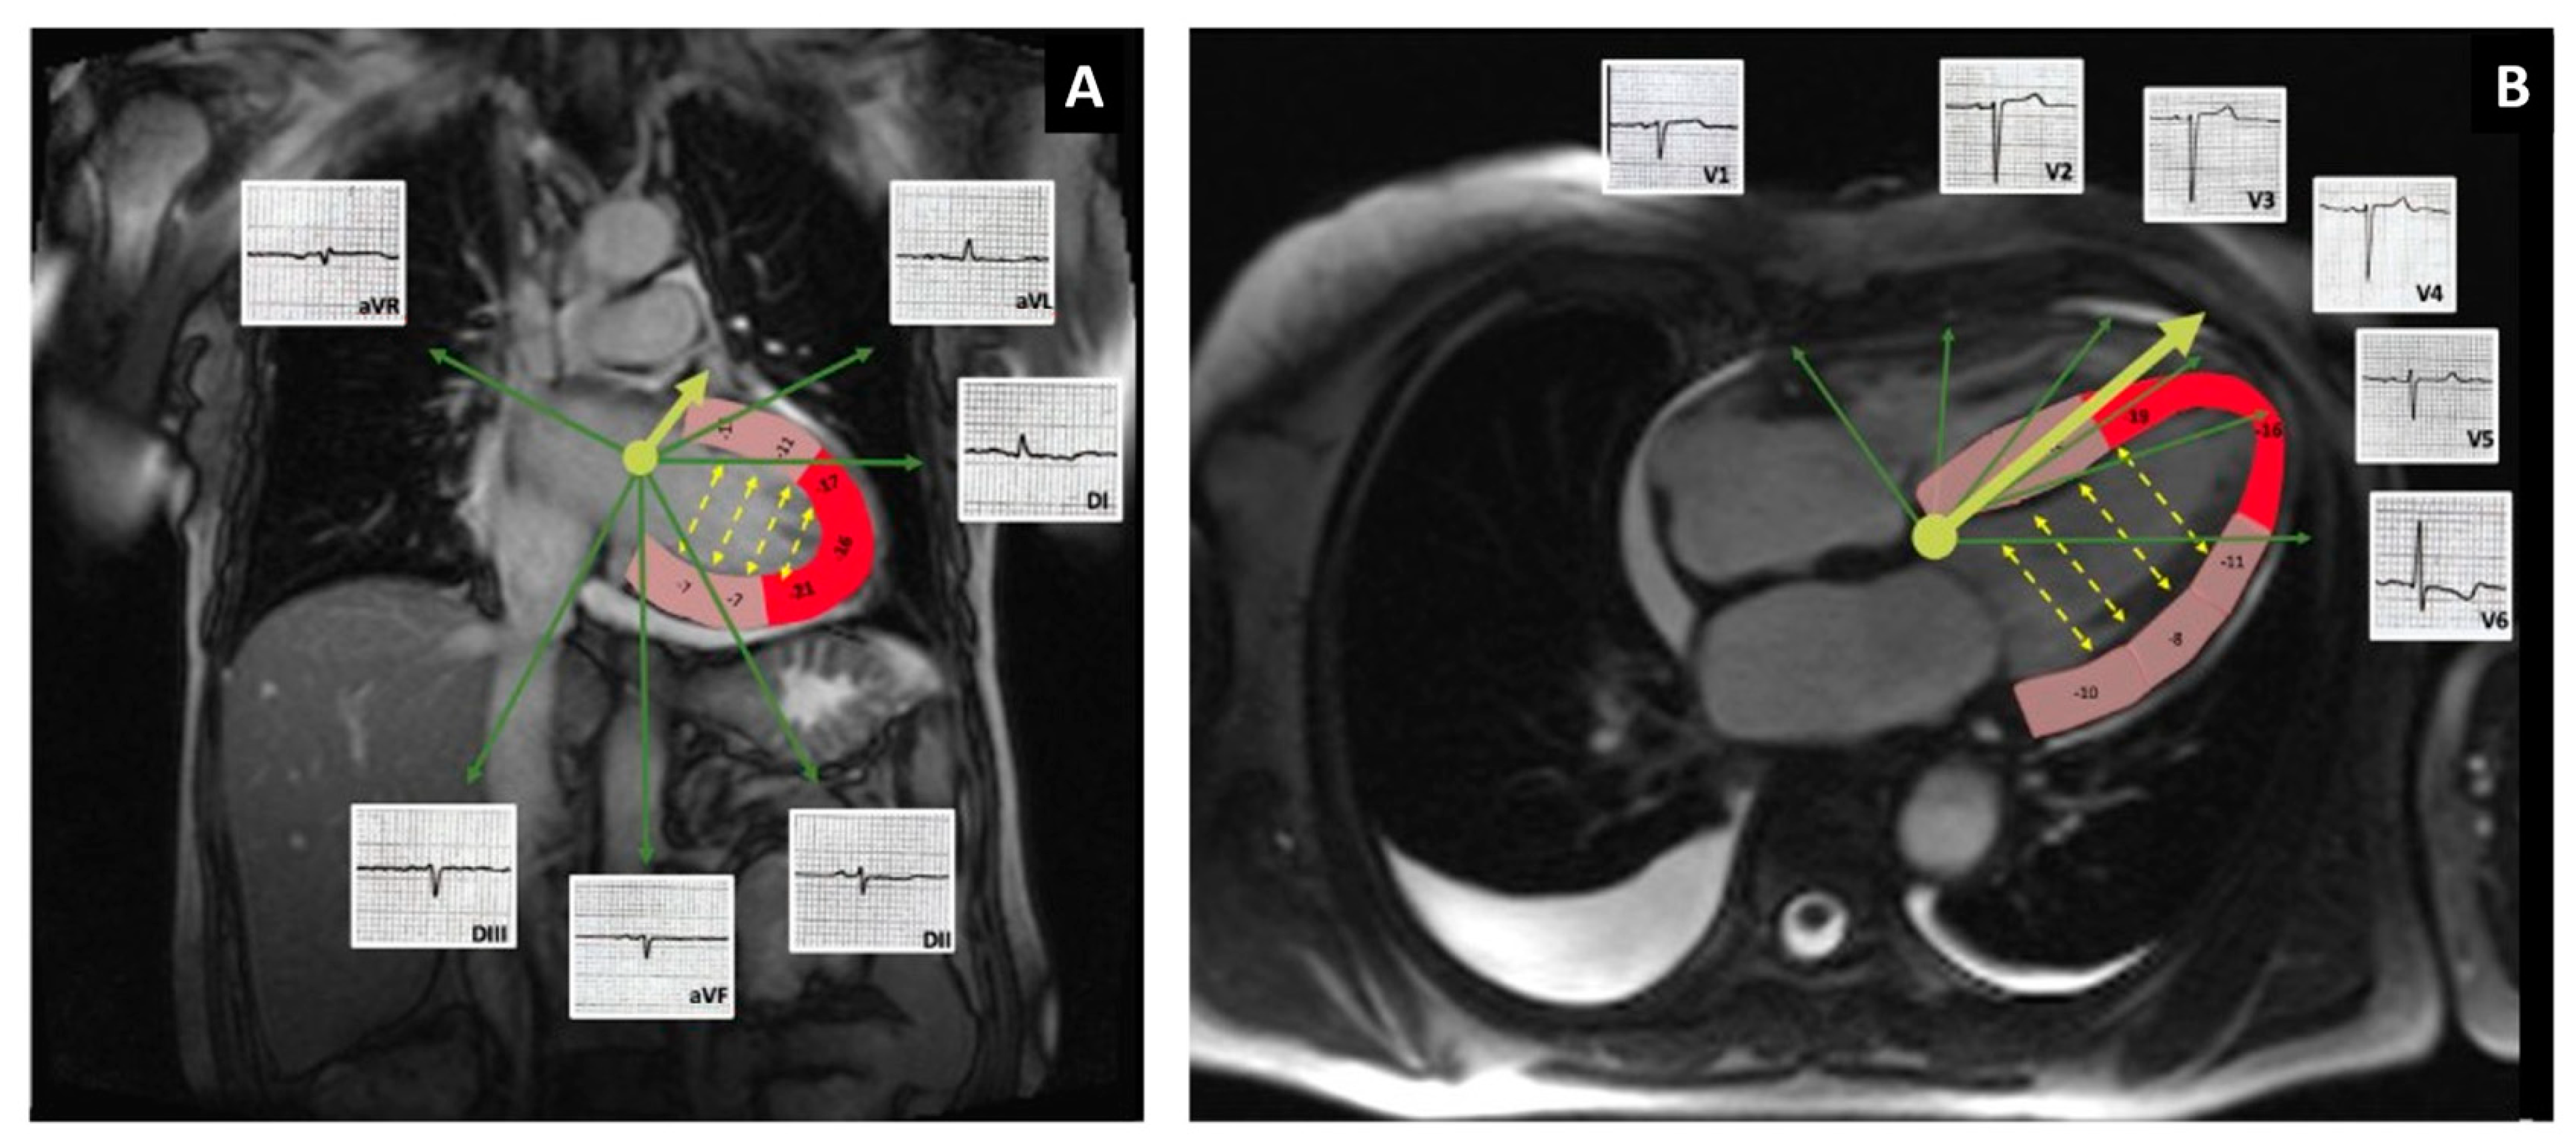

2. Case Report

3.1. QRS Voltage